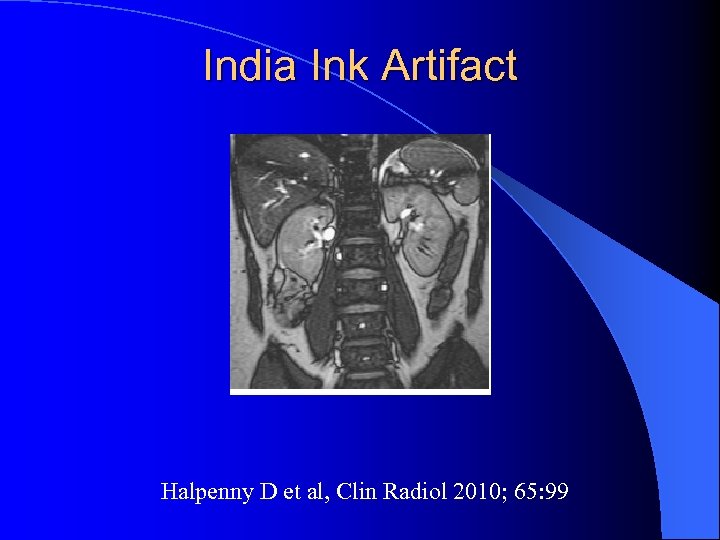

India Ink artifact l Perte de signal linéaire à la jonction graisse /eau – A la jonction tumeur / parenchyme – Dans la tumeur entre les plages graisseuses et non graisseuses Israel GM et al, AJR 2005; 184: 1808

India Ink artifact l Perte de signal linéaire à la jonction graisse /eau – A la jonction tumeur / parenchyme – Dans la tumeur entre les plages graisseuses et non graisseuses Israel GM et al, AJR 2005; 184: 1808

India Ink Artifact Halpenny D et al, Clin Radiol 2010; 65: 99

India Ink Artifact Halpenny D et al, Clin Radiol 2010; 65: 99